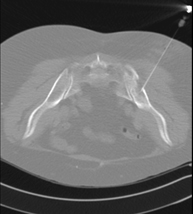

Prova que consisteix en obtenir una mostra de teixit de lesions toràciques, com per exemple masses pulmonars, mediastíniques, lesions òssies, etc. Per això s'administra anestèsia local sobre la zona de punció, que es realitza amb agulles de calibre fi. Tot el procediment es realitza controlat amb imatges obtingudes per tomografia computaritzada (TC) en diversos moments de la punció, mitjançant un equip de Fluoroscòpia-TC. Després de la prova, el pacient resta unes hores hospitalitzat. És necessari portar proves de coagulació abans de la punció. - Biòpsia tòrax guiada per TC

Consisteix en obtenir una mostra de teixit d'una determinada lesió toràcica, com per exemple del pulmó, del mediastí, de l'estern, etc. A vegades es realitza sota sedació, amb l'ajuda de l'equip d'anestèsia. S'utilitzen agulles que permeten l'obtenció d'un cilindre de la lesió a estudiar que s'enviarà a Anatomia Patològica per a la seva anàlisi histològica. Tot el procediment es realitza controlat amb imatges obtingudes per tomografia computaritzada (TC) en diversos moments de la biòpsia, mitjançant un equip de Fluoroscòpia-TC. Després de la prova, el pacient resta hospitalitzat per controlar la seva evolució. És necessari portar proves de coagulació abans de la punció. - TC Columna Dorsal